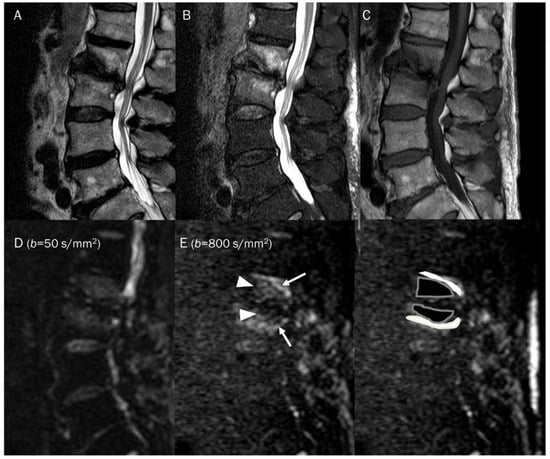

7.4. Vertebral Endplate Changes